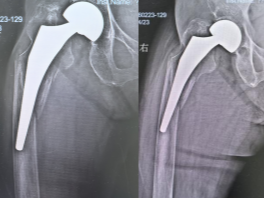

患者术前 X 线片 患者术后X线片

在多学科专家的紧密协作下,手术团队顺利为患者完成手术。术后,骨科三病区护士长杨洁带领护理团队实施精细化护理,高磊副主任医师、拓一帆主治医师、周鑫住院医师共同负责精准治疗与病情管理,患者恢复平稳,各项指标持续好转,最终康复出院。此次成功救治,充分彰显了医院在复杂髋关节翻修领域的技术实力与多学科协同作战的综合能力。